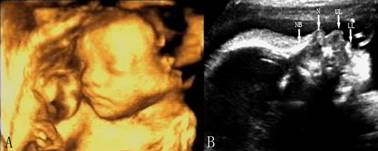

胎儿面部检查并不是胎儿常规检查的内容。在适当的断面上和胎儿体位、羊水等适宜的条件下灵活、综合采用二维、三维等显示方法可以显示胎儿面部结构(图1A),显示出胎儿的双眼、鼻、唇、人中、面颊、及下颌、耳等,实时动态扫查时可显示胎儿在宫内的表情(如眨眼)、张嘴、吸吮、抚面等动作,在发现某些结构异常和遗传学超声检查中具有重要的意义。

正中矢状面检查可以显示典型的胎儿面部侧方剪影图像,由上向下显示前额、鼻背、鼻骨(NB)、鼻尖(N)、口唇(L)、下颌等部位均可显示,并显示其结构和连续关系(图1B),实时动态扫查时可显示胎儿在宫内的表情(如眨眼)、吸吮等动作。

图1胎儿面部三维(A)及矢状面(B)声像图